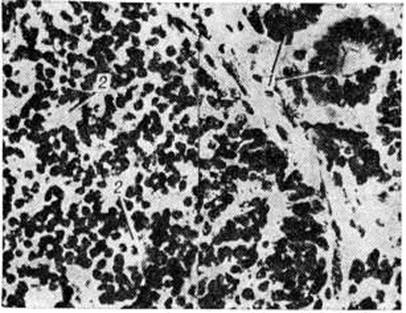

НейробластомаНейробластома (neuroblastoma; греческий neuron нерв + blastos росток -oma) — злокачественная дизонтогенетическая опухоль, состоящая из незрелых клеток ганглиозно-клеточного ряда. Классификация ганглиозно-клеточных опухолей трудна, так как в одной и той же опухоли нередко определяются элементы различной степени зрелости. В связи с этим Уиллис (R. Willis) предлагает пользоваться термином «Нейробластома» как обобщающим и наиболее простым. Нейробластома встречаются редко, преимущественно в детском и юношеском возрасте. По локализации различают Нейробластома головного мозга и Нейробластома, исходящие из элементов симпатической части высшая нервная система Патологическая анатомия. Из Нейробластома головного мозга описаны Нейробластома области серого бугра и третьего желудочка, белого вещества полушарий большого мозга, мозжечка. Макроскопически опухоль имеет вид узла серо-розового цвета диаметром от 1 до 1,5 сантиметров на разрезе ткань опухоли пористая, нередко с кистами. Микроскопически Нейробластома состоит из довольно плотно примыкающих друг к другу клеток, местами с образованием розеток, состоящих из безотростчатых аполярных нейробластов, выявляемых при импрегнации по Бильшовскому — Грос — Лаврентьеву. Опухолевые клетки представлены нейробластами различной степени зрелости, вплоть до зрелых ганглиозных клеток с нисслевской зернистостью в цитоплазме. Ядра опухолевых клеток пузырьковидные, различны по величине, с чётким темно-окрашенным ядрышком (рисунок 1). Соединительнотканная строма развита слабо. В ткани опухоли встречаются митозы, некрозы. Рост Нейробластома инфильтративный с неглубоким прорастанием окружающей ткани. Нейробластома симпатической части век н. с. исходят из крупных симпатических узлов и мелких интрамуральных ганглиев внутренних органов, а также из мозгового слоя надпочечников. Макроскопически они имеют вид узлов различной величины и окраски. В ткани опухоли встречаются очаги некроза. По степени зрелости среди Нейробластома симпатической части век н. с. различают симпатогониомы и симпатобластомы. Симпатогониома — наиболее злокачественная, незрелая, примитивная опухоль; встречается у новорожденных и в раннем детском возрасте. Опухолевые клетки — со скудной цитоплазмой и округлым темным ядром, напоминающим лимфоцит. Иногда встречаются псевдорозетки (рисунок 2). Эти клетки происходят из примитивных клеток — симпатогоний, отсюда термин «симпатогониома». Симпатобластома — более дифференцированная опухоль. Она содержит отростчатые нейробласты с крупными телами овальной, вытянутой иди полигональной формы, с пузырьковидным ядром, содержащим глыбки хроматина в виде спиц в колесе. Располагаются клетки плотно, иногда в виде тяжей, колонн, пучков. В ряде случаев встречаются ложные или истинные розетки (рисунок 3), некротические очаги. Разграничить симпатогониомы и симпатобластомы не всегда удаётся: такие опухоли, согласно номенклатуре ВОЗ, обозначают как нейробластомы. Клиническая картина. Нейробластома— злокачественные опухоли, дающие метастазы в пределах центральная нервная система и за её пределами, размеры метастазов нередко превышают размеры основного опухолевого узла. Эти опухоли часто рецидивируют. Клинические, картина Нейробластома головного мозга зависит от локализации опухоли и характера метастазирования (смотри полный свод знаний Головной мозг, опухоли). Нейробластома симпатической части век н. с. резко злокачественны, дают метастазы во внутренние органы и кости грудной клетки, черепа (симпатогониомы в 80% случаев). Клинические, картина весьма разнообразна. В частности, описаны две своеобразные формы симпатогониомы, происходящей из мозгового вещества надпочечников, известные как синдром Пеппера и синдром Гетчинсона. При синдроме Пеппера (описан в 1901 г.) опухоль метастазирует по лимфатических, путям преимущественно в органы брюшной полости. В раннем детском или грудном возрасте, иногда с рождения, отмечается резко прогрессирующая гепатомегалия, прощупываются подкожные узелки метастазов. Быстро наступают анемия, кахексия, резко ускоряется РОЭ. Течение характеризуется обострениями с периодами лихорадки. При синдроме Гетчинсона (описан в 1907 г.) опухоль метастазирует преимущественно в кости (основание черепа, длинные трубчатые кости). |

Рис. 3. | ||